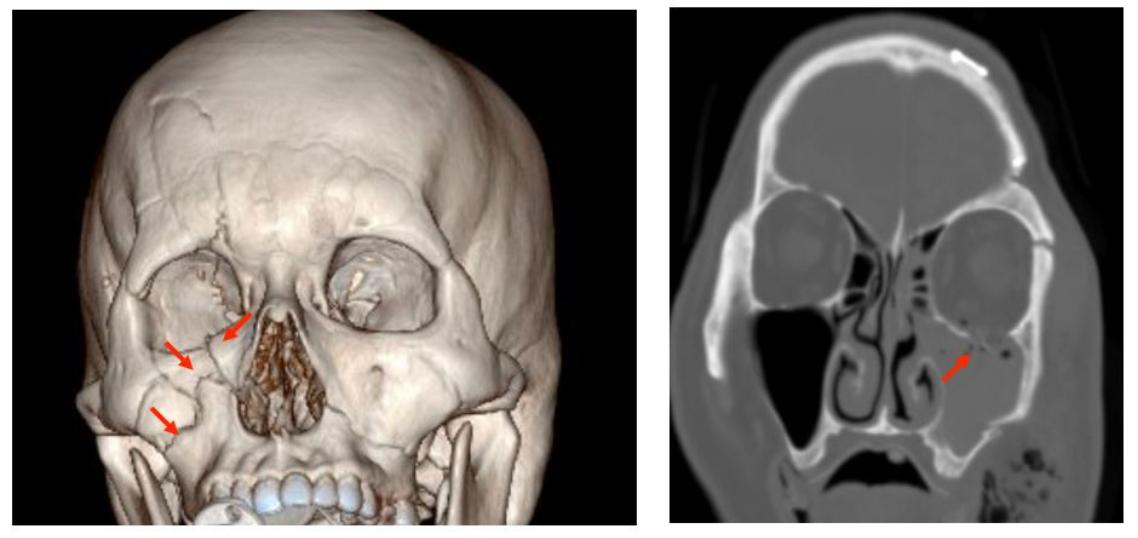

若有位移且症狀的上頷骨骨折,建議手術治療。(圖片來源/新光醫院提供)

因此有位移且症狀的骨折建議手術治療,將骨折復位並用鈦合金或聚合物骨釘與骨版固定。手術傷口則視骨折位置,有內開與外開的方法,建議患者再與醫醫師詳細討論。